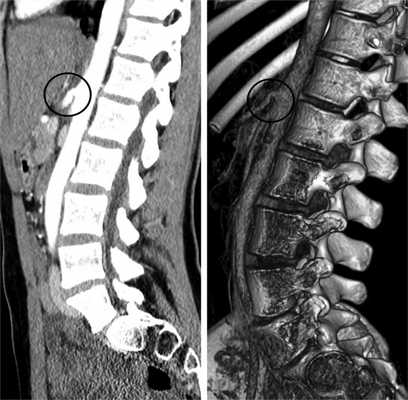

Двум пациентам проведено контрольное обследование в позднем послеоперационном периоде: УЗИ в режиме импульсно-волновой допплерографии, МСКТ с внутривенным усилением (рис. 5) и ангиография (рис. 6). Клинически в обоих наблюдениях отмечалось уменьшение интенсивности, частоты и продолжительности болевого синдрома.

Рис. 5. Мультиспиральная компьютерная томограмма с внутривенным усилением и 3D-реконструкция после операции.

Рис. 6. Ангиограмма (целиакограмма) в боковой проекции до (а) и после (б) операции.